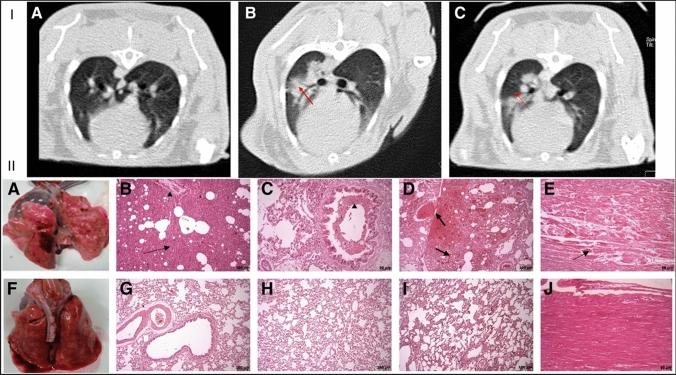

COVID-19 has severely devastated many lives across the globe. It has been speculated that stem cell-based therapy for COVID-19 treatment could be able to subsidize the effects. In preclinical and clinical studies, stem cell-based therapy has successfully eliminated inflammatory cytokines in ALI, ARDS, and COVID-19. Clinical trials have produced a variety of promising results for validating stem cell therapy in COVID-19 patients. For instance, exosome-based therapy (ExoFlow) showed an 87% survival status, and MSC-based therapy (Mesoblast) achieved an 83% survival rate in moderate to severe COVID-19 patients. This review debates the advantages of cell-free therapy, i.e., stem cell-derived exosome-based therapies, over stem cell-based therapy. This review aims to question whether the immunomodulatory effect of stem cells differs based on their origin and also tries to find possible answers for the best stem cells for treating SARS-CoV-2 infection. The role of stem cells and their extracellular vesicles in the upregulation of regulatory immune cells, growth factors (EGF, FGF, VEGF), and anti-inflammatory cytokines (IL-6, INF-α, galectin-1, notch-1, PDL-1) that promote the tissue regeneration at the injured site. The right side of the image depicts the downregulation of inflammation-inducing immune cells, pro-inflammatory cytokines, and chemokines that could also enhance COVID-19 therapy.

新型冠状病毒肺炎(COVID-19)在全球范围内严重影响了许多人的生活。有人推测,基于干细胞的治疗方法可能有助于缓解 COVID-19 的影响。在临床前和临床研究中,基于干细胞的治疗方法已成功消除了急性肺损伤(ALI)、急性呼吸窘迫综合征(ARDS)和 COVID-19 中的炎症细胞因子。临床试验为验证 COVID-19 患者的干细胞治疗提供了多种有前途的结果。例如,基于外泌体的治疗(ExoFlow)显示出 87%的存活状态,基于间充质干细胞的治疗(Mesoblast)在中度至重度 COVID-19 患者中达到 83%的存活率。本综述讨论了无细胞治疗(即基于干细胞衍生的外泌体治疗)优于基于干细胞的治疗的优势。本综述旨在质疑干细胞的免疫调节作用是否因其起源而异,并尝试为治疗 SARS-CoV-2 感染的最佳干细胞寻找可能的答案。干细胞及其细胞外囊泡在调节性免疫细胞、生长因子(EGF、FGF、VEGF)和抗炎细胞因子(IL-6、INF-α、半乳糖凝集素-1、 Notch-1、PDL-1)的上调中的作用,这些因子促进受损部位的组织再生。图像的右侧描述了炎症诱导免疫细胞、促炎细胞因子和趋化因子的下调,这也可能增强 COVID-19 的治疗效果。